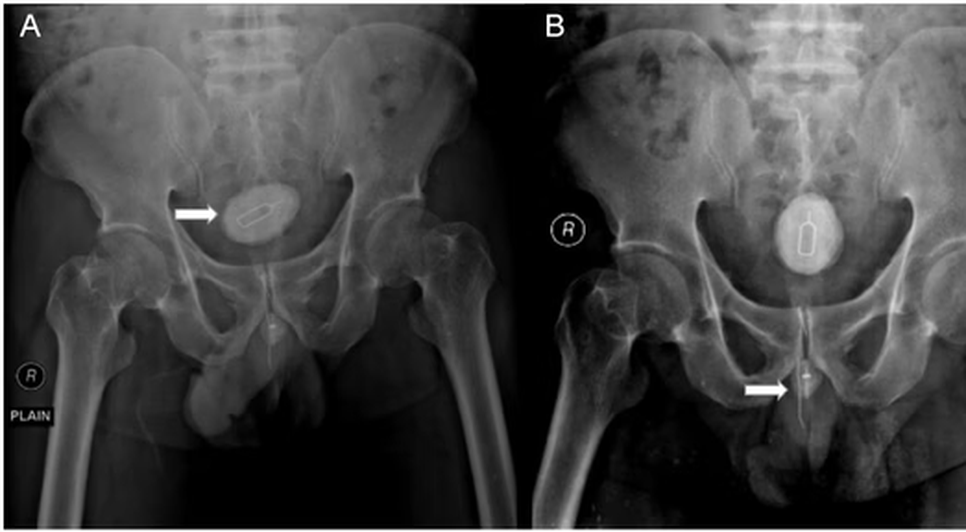

Homem é submetido a cirurgia para retirar chip, cabo elétrico e elástico introduzidos no pênis 12/04/2024 as 17:57 Receba notícias em seu WhatsApp Participe da nossa comunidade